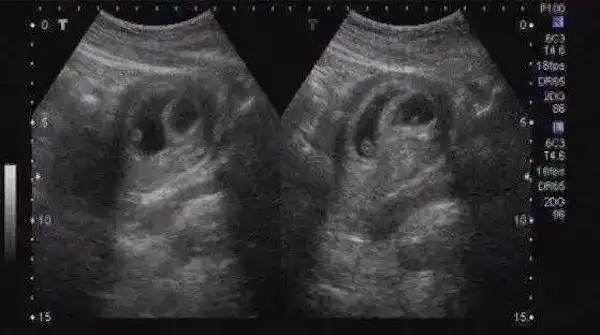

怀孕50天,超声看孕囊能看出男女?医生这样说|胎儿|b超|羊水_网易亲子